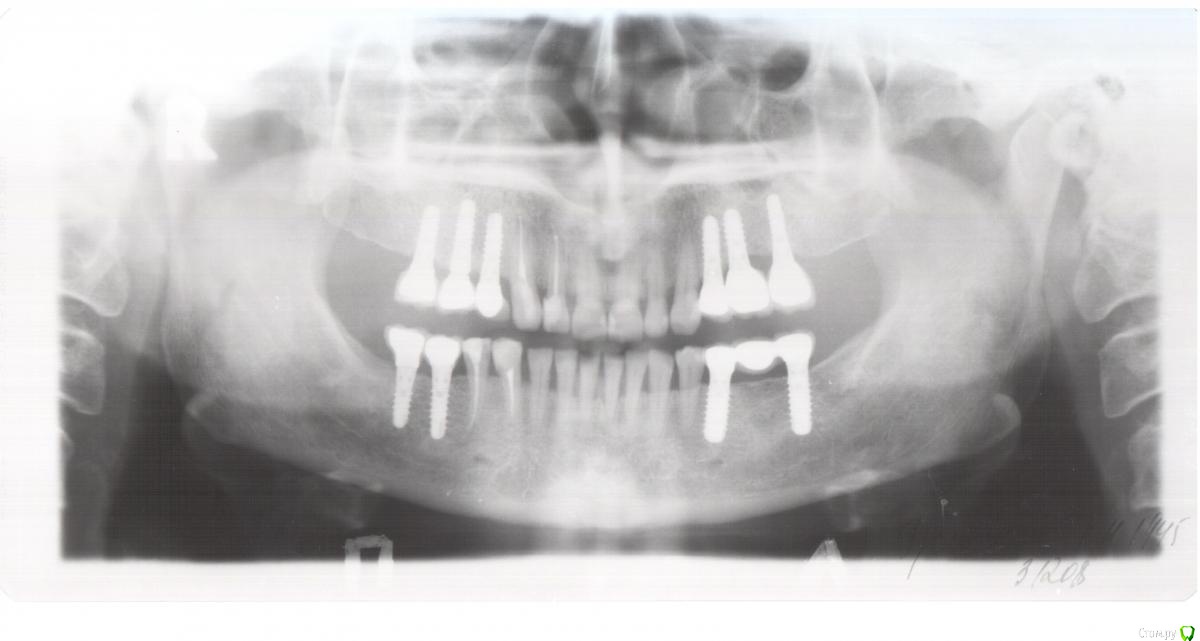

alekszander Опубликовано 25 февраля, 2016 Поделиться Опубликовано 25 февраля, 2016 Пациентка 45-го г.р. Из анамнеза: имплантация была проведена более 10 лет назад. Имплантаты на тот момент очень популярные и ставил человек минимум КМН на тот момент, а может уже и выше. Со слов пациентки - имплантат 1.4 закачался и выпал несколько недель назад. Пациентка никаких болей не отмечает. Общее соматическое состояние - удовлетворительное. Сахар на границе +- от нижней нормы, но диабет не ставят. Были проблемы с щитовидной железой (что точно не помнит), насколько понял из анамнеза - тиреоидит вроде. Когда-то была язва (более 20 лет назад) Не курит, не пьет. В целом жизнерадостная женщина и даже не выглядит на свой возраст. Вопрос как так? В 3-м квадранте все гуд, в остальных такая опа. Со стороны полости рта - имплантаты покрыты слизистой до уровня МК коронок. На момент обращения при пальпации обильное гнойное отделяемое, но болевых ощущений нет! Назначил АБ+НПВС+АГ+ХГ местно. Сегодня пришла: гной сохранен только в области 2.3,2.4,2.5,2.6 но уже скудное отделяемое. Пальпация по прежнему безболезненная. Слизистая без грануляций, розового цвета (поверхностно) Из вариантов - по хорошему: на выход имплантаты 1,2,4 квадранты+зубы 1.3,2.3. Временные съемные. Общий анализ крови и совместное наблюдение с эндокринологом. По поводу повторной имплантации чет- сомневаюсь, но нужны будут анализы. По плохому (умаляет пациентка,т.к возраст уже такой, что повторно не готова а съемное не хочется) сохранить имплантаты и диспансерное наблюдение. Правда тут у меня вопрос в голове, а что делать с 1.4,1.3,2.3 в плане протезирования?.... Коллеги прошу помощи, ситуация не однозначная. Прилагаю ОПТГ через год после протезирования и 2 недельный снимок. Ссылка на комментарий

alekszander Опубликовано 26 февраля, 2016 Автор Поделиться Опубликовано 26 февраля, 2016 Прилагаю фото в полости рта (прошу прощения фото на мыльницу Leica) - ретракторов и зеркал пока нет. Ссылка на комментарий